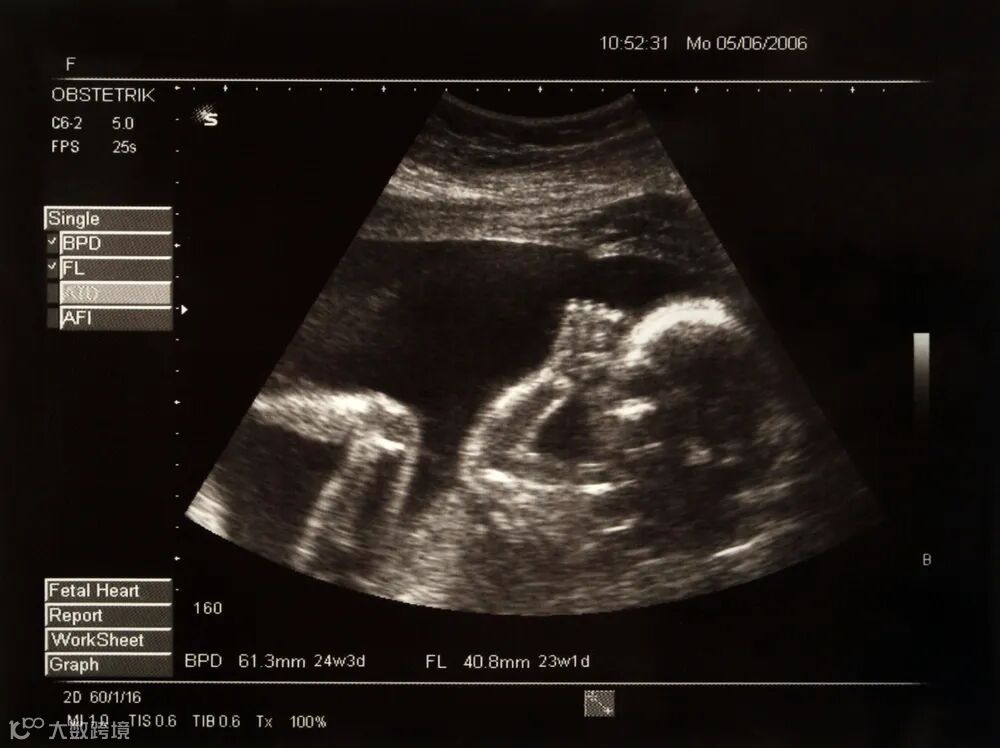

小李和小黄(化名)结婚多年,一直怀不上孩子。两人年龄越来越大,于是选择了试管婴儿这个方法怀孕。